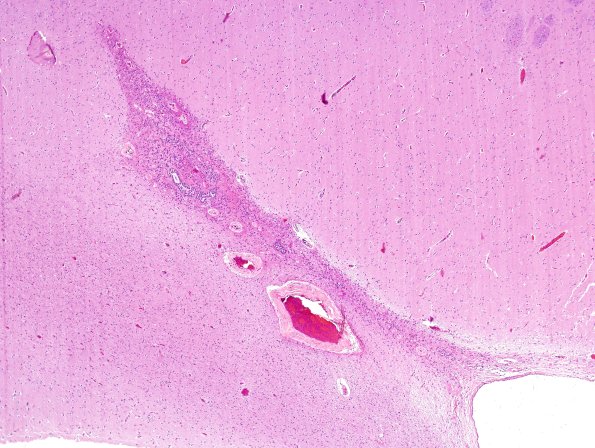

Washington University Experience | BASIC PROCESSES | Ependymal Fusion Seam | 10A1-Ependymal-seam-Case-17-H-E-1.jpg

10A1,2 It continues to surprise me how abnormal the ependymal seam can be, especially the microvasculature. (H&E)